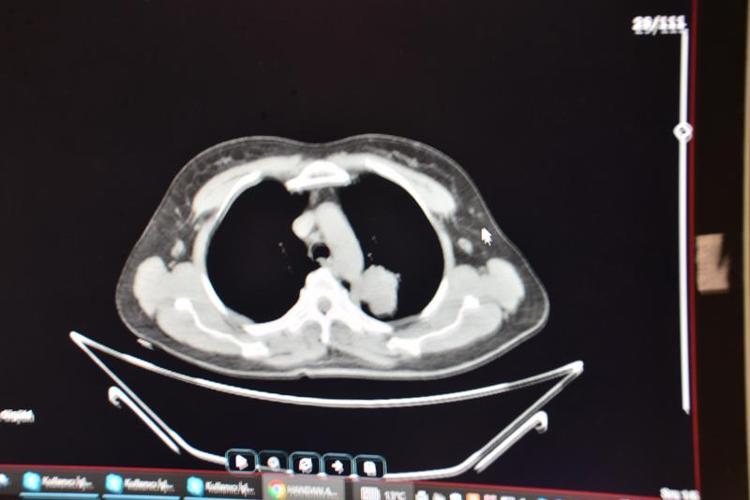

Adana'da göğüs ağrısı ve öksürük şikayetleriyle başvurduğu hastanede yapılan ileri tetkiklerde akciğerinde kitle saptanan ev kadını Handan Aras'a (55) Balcalı Hastanesi Göğüs Cerrahi Bölümü'nde akciğer kanseri teşhisi kondu. Doç. Dr. Alper Avcı ve ekibi tarafından ameliyat edilen Aras'ın akciğerindeki tümörlü doku alındı. Kısa sürede sağlığına kavuşan Aras, "Çok sigara kullanan biriydim. Ameliyat olduğumdan beri hiç içmedim. 30 yıl sigara içtim ama artık kullanmayı düşünmüyorum. Bu kadar acıyı yaşadıktan sonra imkansız. Kimse benim gibi bir hata yapsın istemiyorum" dedi.

Yakın zamana kadar büyük çoğunlukla erkeklerde görülen akciğer kanserinin son yıllarda özellikle kadınlarda sigara kullanımına bağlı olarak artışa geçtiğine dikkati çeken ÇÜ Tıp Fakültesi Balcalı Hastanesi Göğüs Cerrahi Anabilim Dalı Öğretim Üyesi Doç. Dr. Alper Avcı, "Hastamız da sigara içen bir gruptandı. Yaptığımız ameliyatla tümörü tüm dokusuyla birlikte temizleyebilmek adına sol akciğer üst lobunu almak durumunda kaldık.

Bölgede tümörün yayılma ihtimali olan lenf bezelerinin de hepsini topladık. Şu an durumu gayet iyi ve onkolojik tedavisi devam ediyor. Son yıllarda akciğer kanseri kadınların sigara içme alışkanlıklarının değişmesine bağlı olarak bu grupta ciddi anlamda artış gösterdi. Ülkemizde, kadınlarda akciğer kanseri görülme durumu diğer kanserlere göre 4’üncü sıraya kadar yükseldi. Yani yüzde 10'ların bile altında olan görülme sıklığı, yüzde 15-20'lere tırmandı" diye konuştu.

Detaylı radyolojik incelemeler sonucunda akciğerinde bir kitle olduğu ortaya çıkıyor. Daha sonra onun tanısı ve tedavi planlaması yapılıyor. Kesinlikle sigaradan uzak durulmasını tavsiye ediyoruz. Zira sigara her halükarda akciğer kanserinin temelinde ispatlanabilmiş en bariz etkendir" ifadelerini kullandı.